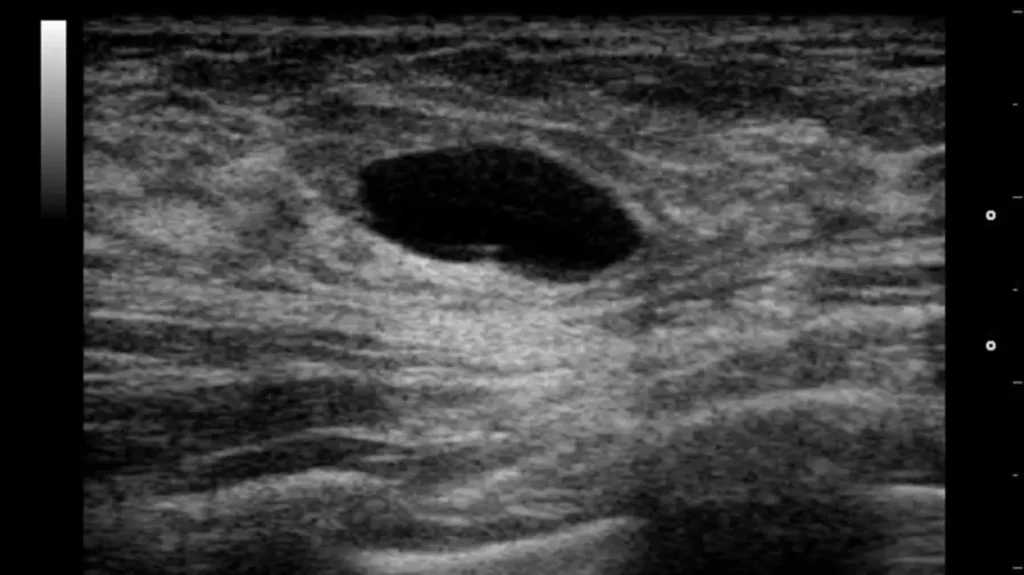

Фотография предоставлена Nevit Dilmen/Wikimedia Commons

Доброкачественные кисты могут образовываться, когда жидкость скапливается около ваших грудных желез. Они могут вызывать боль или болезненность в пораженной области.Хотя кисты груди не являются раковыми, существует множество других возможных более серьезных причин появления уплотнения в груди. Важно знать, как обычно ощущается ваша грудь, чтобы вы знали об изменениях. Таким образом, вы с большей вероятностью сразу заметите изменения.Вам следует попытаться записаться на прием к врачу, если:вы обнаружили новое уплотнениеобласть вашей груди заметно отличается от остальнойуплотнение изменяется или увеличиваетсявы заметили неожиданные выделения из соскау вас втянутый сосок, и он не всегда был втянутым Ганглионарная киста